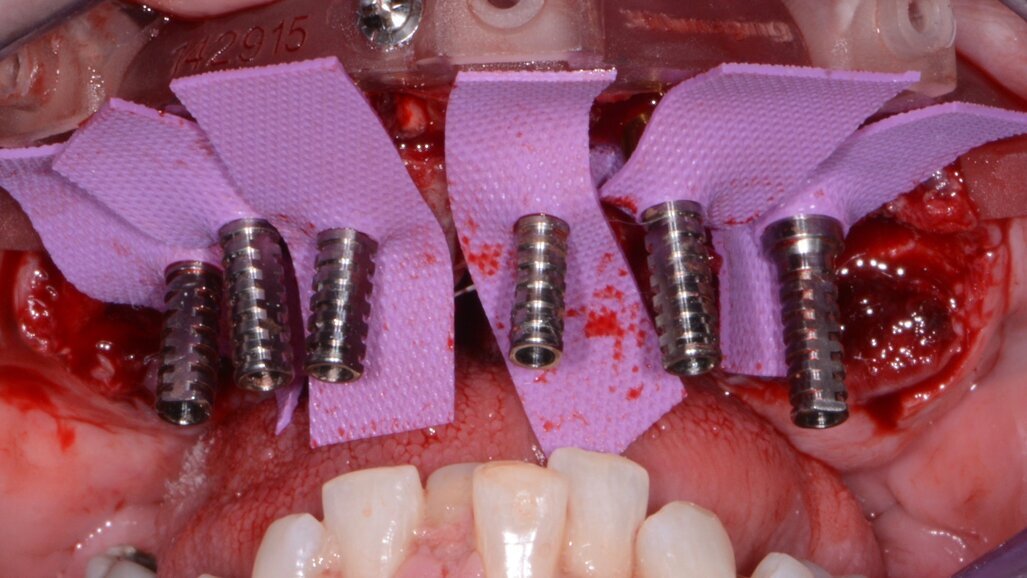

Once the virtual plan had been orchestrated and fully confirmed, the next appointment was for the planned surgery with all the necessary components for the guided surgical approach. The patient was appropriately sedated with intravenous medications, and local anaesthesia was administered in both arches. The tissue was then reflected using the Reflector instrument (GoldenDent) so that the bone levelling surgical guide would be fully seated and fixed with its respective retention screws (Fig. 7). After the positioning of the surgical guide, the maxillary teeth were atraumatically extracted utilising the Physics Forceps (GoldenDent). Once the appropriate bone levelling had been accomplished with the surgical handpiece, the implant surgical guide (Fig. 8) was positioned into the bone levelling guide and the osteotomies for the implants were initiated with a designated pilot drill in the implant system’s guided surgery drill kit (Adin Dental Implant Systems; Fig. 9). Using precise orientation, depth and direction, the guided surgery kit provides fast, effective and predictable preparation and placement of dental implants for dental practitioners. It also features easy-to-follow layouts along containing self-centring drills with built-in stoppers. The unique design of the guide, employing ActiveFlow irrigation technology, directs cooling saline through the guide, ensuring that irrigation reaches the bone and thereby reducing the possibility of bone heating throughout the procedure.

Utilising the Mont Blanc surgical handpiece and AEU 7000 surgical motor (both Aseptico) at a speed of 800 rpm with copious amounts of sterile saline, sequential drill preparation was initiated. Once the osteotomies were complete, the drivers in the guided kit (Adin Dental Implant Systems; Fig. 10) were used to place the dental implants with precise timing so that the flat portion of the internal hex was positioned ideally for receiving the multiunit abutments.

A baseline implant stability quotient (ISQ) reading was taken of these implants utilising the Penguin RFA unit (Aseptico). Since the initial readings were all above 70 ISQ, and the quality of bone after levelling was good, multi-unit abutments (Adin Dental Implant Systems) were tightened into the Touareg-OS dental implants to 30 Ncm, followed by temporary cylinders to 15 Ncm.

Fig. 9: Maxillary implant surgical guide.

Fig. 11: Maxillary temporary cylinders isolated.

The maxillary provisional restoration was tried in to verify a passive fit over the temporary abutments. Once fit had been confirmed, trimmed dental dam pieces were placed to avoid the restoration (Fig. 11) from locking on during the relining procedure with REBASE III FAST set hard reline material (Tokuyama Dental). After the material had polymerised, the immediate provisional restoration was removed and any access material was removed with the Torque Plus laboratory handpiece (Aseptico) and an acrylic bur (Komet). The same procedures were accomplished in the mandibular arch (Figs. 12–14). Once trimmed and polished, the provisional restorations were seated and tightened with a torque wrench at 15 Ncm (Fig. 15). The access openings were filled in three-quarters of the way with Teflon tape, followed by Cavit filling material (3M ESPE). A postoperative panoramic radiograph was taken immediately after the surgery (Fig. 16).